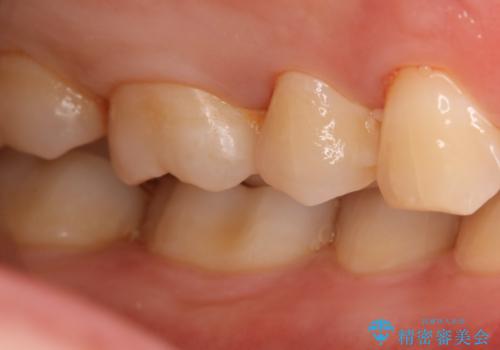

- 右上6番の虫歯治療を主訴に来院された患者様です。

切削量・形態を考慮し、セラミックインレーでの治療を計画しました。

保険の材料が劣化し中で虫歯が進行していたので、全て取り除いた上で形を整え型をとりインレーをセットしています。